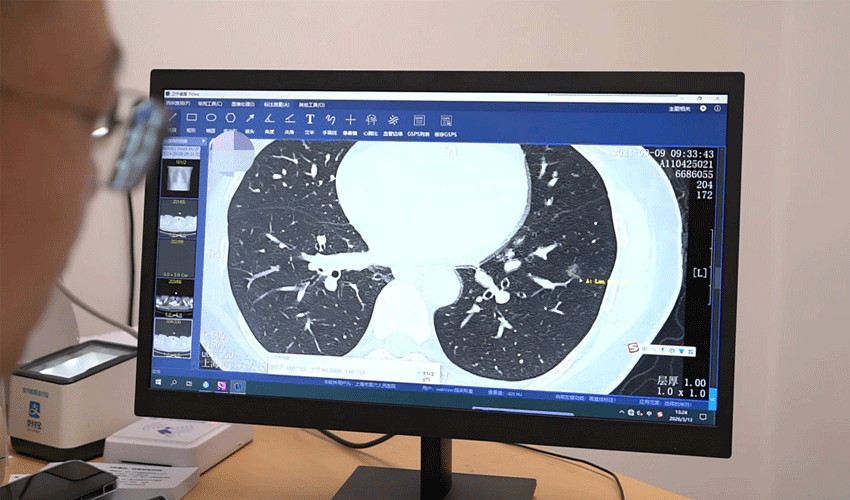

近年来,体检中发现肺结节的人群日益增多,不少人陷入“谈结节色变”的焦虑。谢晓指出,肺结节是直径小于3厘米的肺部阴影,可分为实性、亚实性等类型,80%以上为良性,如同皮肤上的痣,是肺部自我修复留下的“疤痕”,无需过度恐慌。

他强调,肺结节的“高检出率”与“低恶性率”并存是当前临床典型现象。判断结节恶性概率需综合三大核心指标:大小、形态及动态变化:直径≤8毫米的“微小结节”,恶性概率低于5%,建议每6至12个月进行低剂量CT随访; 直径>8毫米的结节,需缩短随访间隔或进一步干预;形态上,良性结节多呈边缘光滑的“乒乓球征”,而恶性结节常具备“荷包蛋征”“月牙征”等特征;生长速度方面,若3至6个月内结节增长超过2毫米,需高度警惕恶性可能。

谢晓特别强调,肺结节恶性概率与个体危险因素密切相关,40岁以上人群、长期吸烟者(吸烟指数≥20包年)、有肺癌家族史者及慢性肺部疾病患者,需每年进行低剂量胸部CT筛查。若发现可疑结节,需进一步行薄层CT扫描、三维重建或AI辅助诊断,提高恶性结节检出率。

谢晓曾接诊一位52岁男性患者,该患者有30年吸烟史,体检发现右肺上叶直径12毫米的混合磨玻璃结节,形态呈“荷包蛋征”。经多学科会诊(MDT),患者选择机器人辅助肺段切除术,成功切除病灶并保留大部分右肺上叶。术后病理证实为微浸润腺癌(早期肺癌),因干预及时,患者无需术后化疗,仅需定期随访,3个月后已恢复正常生活。